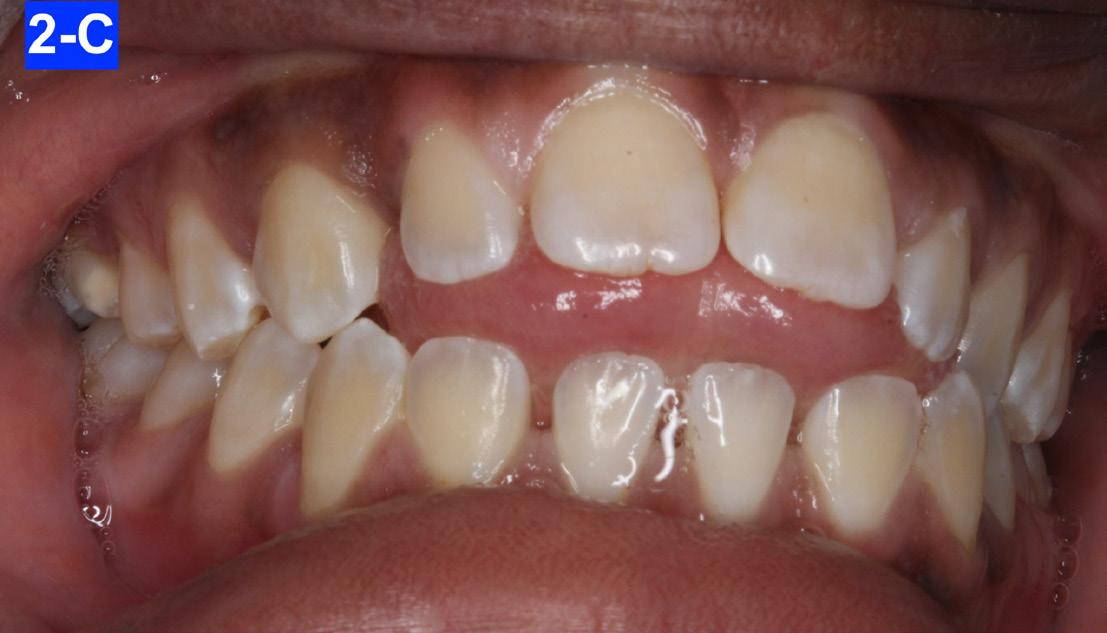

Mini-esthetic appraisal revealed competent full upper and lower lips and an incongruent smile arc to the lower lip. The patient’s posed smile revealed negative buccal corridors and a significant anterior open bite. Lips in reposed showed no tooth display. The patient showed signs of a reverse swallowing pattern (Figures 2-A, 2-B, 2-C).

Fig. 2-C: Reverse Swallow

Fig.2-B: Posed Smile